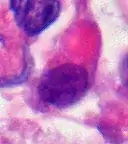

AT/RT and rhabdoid tumor share the term "rhabdoid" because under a microscope, both tumors resemble rhabdomyosarcoma.

Rhabdoid Tumor Cell - 400X Magnification

Histology

The tumor histopathology is jumbled small and large cells. The tissue of this tumor contains many different types of cells including the rhabdoid cells, large spindled cells, epithelial and mesenchymal cells, and areas resembling primitive neuroectodermal tumor (PNET). As much as 70% of the tumor may be made up of PNET-like cells. Ultrastructure characteristic whorls of intermediate filaments are seen in the rhabdoid tumors (as with rhabdoid tumors in any area of the body). Ho and associates found sickle-shaped embracing cells, previously unreported, in all of 11 cases of AT/RT.[18]